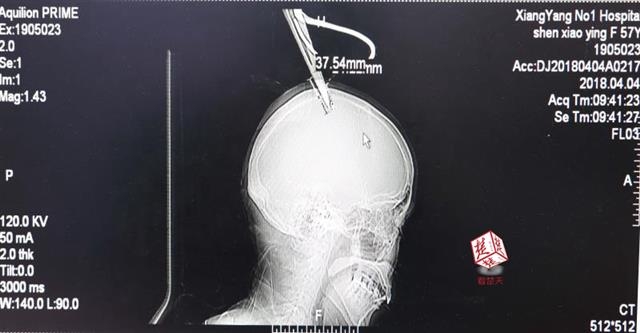

女子顱骨插進(jìn)剪刀 不慌不忙坐公交車就醫(yī)

醫(yī)生檢查發(fā)現(xiàn),剪刀刀尖斜嵌在沈某顱骨里,離腦髓只有兩三毫米。所幸是斜著插進(jìn)去,如果是垂直刺入,很有可能造成癱瘓。

4月4日清晨,襄陽市樊城區(qū)太平店鎮(zhèn)57歲的農(nóng)村婦女沈某,在采摘香椿嫩芽時(shí),綁在竹桿上的剪刀因竹子腐朽不慎折斷,剪刀斜插入頭顱。經(jīng)過及時(shí)搶救,目前脫離生命危險(xiǎn)。

醫(yī)生檢查發(fā)現(xiàn),剪刀刀尖斜嵌在沈某顱骨里,離腦髓只有兩三毫米。所幸是斜著插進(jìn)去,如果是垂直刺入,很有可能造成癱瘓。最終經(jīng)過手術(shù),剪刀被取出,沈某目前仍在ICU進(jìn)一步觀察。